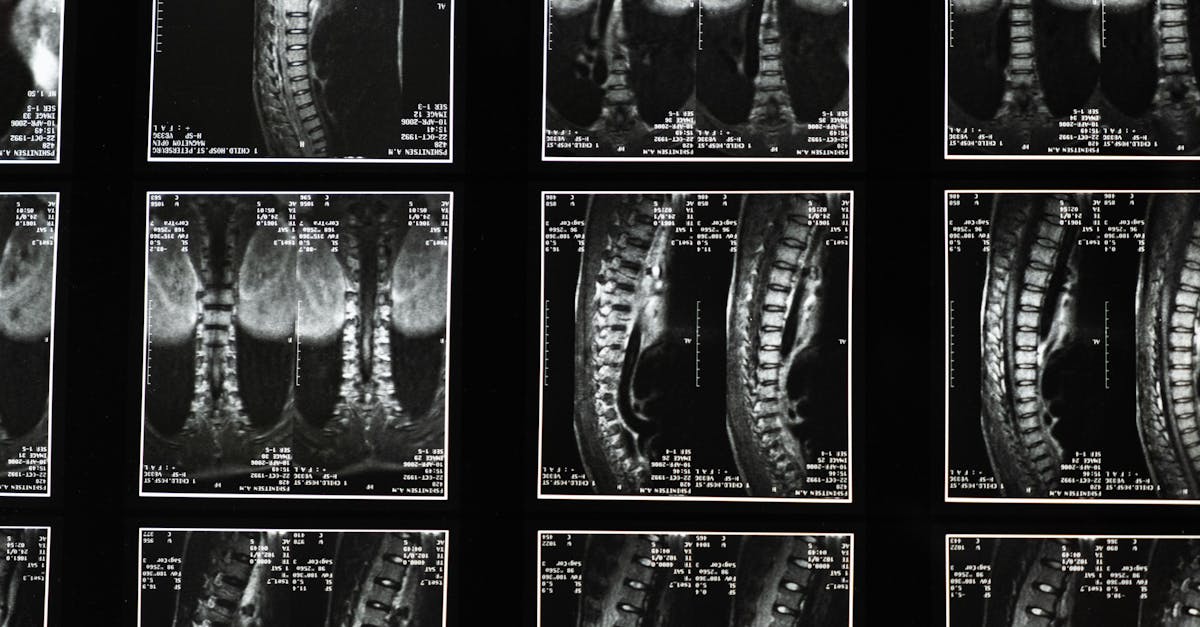

La décompression neurovertébrale est une technique thérapeutique qui vise à soulager la pression exercée sur les structures nerveuses. Elle intervient principalement sur la colonne vertébrale pour permettre aux disques intervertébraux de se réhydrater et de retrouver leur position naturelle. En appliquant une traction douce, cette méthode favorise un environnement propice à la guérison.

La décompression neurovertébrale vise à relâcher la pression sur les nerfs et à restaurer l’alignement de la colonne vertébrale. Cette technique utilise des appareils spécifiques qui étendent doucement la colonne vertébrale, créant ainsi un espace entre les vertèbres. Cette action facilite la circulation sanguine et la décompression des nerfs, ce qui à son tour permet de réduire l’inflammation et de diminuer la douleur.

Le fonctionnement de la décompression neurovertébrale repose sur l’application de forces spécifiques et contrôlées au niveau de la colonne vertébrale. Ces forces permettent d’augmenter l’espace entre les vertèbres, ce qui favorise la circulation sanguine et l’apport de nutriments aux tissus environnants. En réduisant la compression exercée sur les disques intervertébraux, la technique aide également à diminuer la douleur et à améliorer la mobilité.